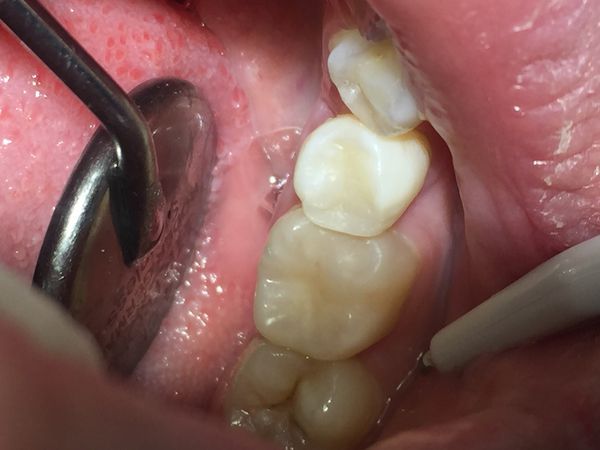

- Пломбировочный материал Ceram наносили послойно, и каждый слой засвечивали в течение 20 секунд. В конце восстановили анатомическую форму зубов.

- Сняли матричную систему, отшлифовали и отполировали пломбы с помощью алмазных боров и полировочных головок. Боковые стенки зубов полировали с помощью металлических и лавсановых штрипсов (абразивных полосок).

- Окклюзию (смыкание зубов) проверили копировальной бумагой. Окончательную полировку пломб провели щёточками и пастой Detatrin Z.